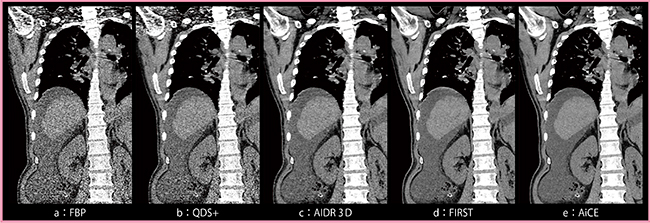

図1は8.7mGyで撮影した腹水貯留のある症例(症例1)で,FBP(a)と比較し, QDS+(b)では臓器の構造境界がボケることなくノイズが大幅に低減されている。一方,1.5mGyの低線量で撮影した小児腹部CTのアキシャル画像(症例2:図2)では,QDS+の画像(b)はFBP(a)よりは良好であるものの,ノイズ低減効果は弱く,ストリークアーチファクトも残存している。

図1,2におけるQDS+(b)とAIDR 3D(c)の画像を比較すると,QDS+で残存していたノイズが,AIDR 3Dではより高いレベルで低減されており,ストリークアーチファクトも大幅に低減されている。

図1,2におけるAIDR 3D(c)とFIRST(d)の画像を比較すると,FIRSTの方が明らかにノイズやアーチファクトが低減されている。ただし,図2をよく見ると,FIRST(d)では肝臓内の軟部組織のテクスチャが粗く,構造が視認しづらい。

図1,2におけるFIRST(d)とAiCE(e)の画像を比較すると,AiCEの方がより高レベルなノイズ低減を実現している。また,FIRSTで問題となっていた軟部組織のテクスチャの粗さも,AiCEでは問題なく,あたかも高線量で撮影したかのような,非常にきめ細やかな画質が得られている。

図1 8.7mGyで撮影した腹水貯留のある症例のコロナル画像(症例1)